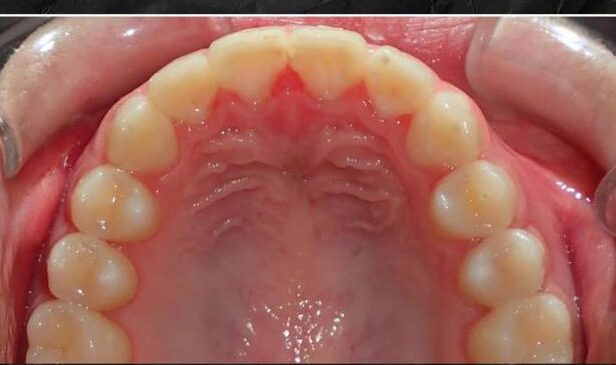

Upper incisor

Orthodontic treatment done on upper front teeth and also expanded the arch into a uniform curve.